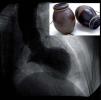

Miocardiopatía de Takotsubo asociada a estrés emocional

Takotsubo cardiomyopathy associated to emotional stress